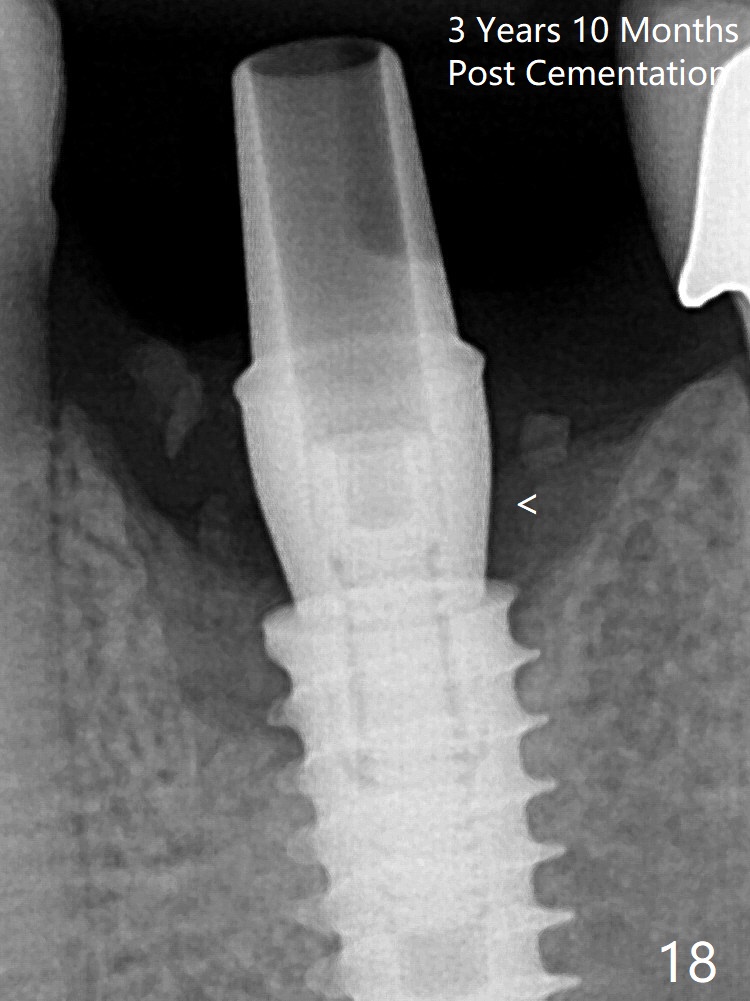

The crown/abutment is loose 3 times (3 months (Fig.14), 11 months (between Fig.14 and 15) and 2 years 3 months post cementation). In spite of being stable 3 years 10 months post cementation, a smaller abutment is placed (Fig.17 (PA), 18 (BW)) with impression for a new crown.